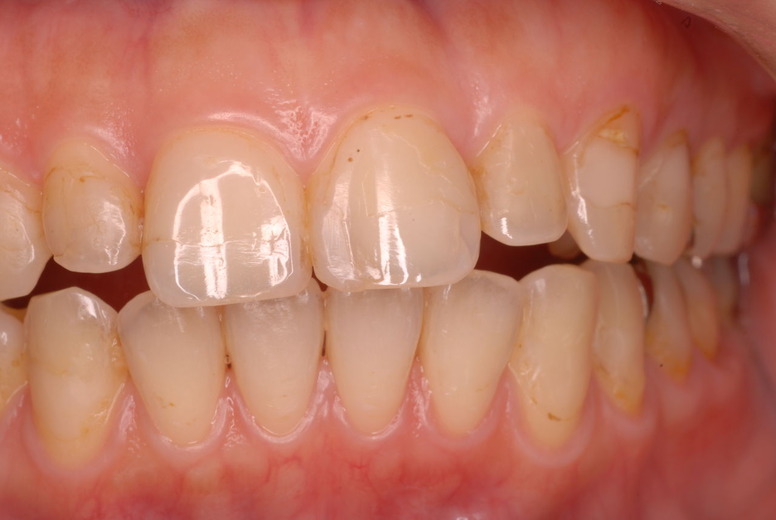

親知らずを取ることを嫌がる方が多いのですが、もし親知らずとその隣の14歳大臼歯の間に虫歯ができたり歯周病を罹患した場合、どれほど治療が大変で再発も起こりやすいか理解できない方がおおいのです。

写真左下の親知らずが痛くなり抜歯しました。その後歯茎を除去して虫歯を露出させる処置を二回ほどしています。

レントゲンでは小さいですが、こう言う虫歯が一番怖いのです。

治療の成功率は極めて悪くすぐ再発しやすいのです。